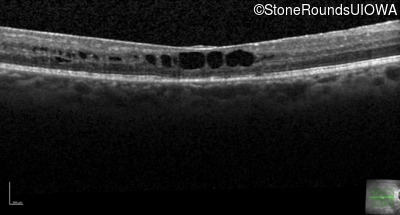

This 43 year old woman first experienced a slight loss of visual acuity at age 23. Fluorescein angiography at that time revealed some vascular leakage from the optic discs and peripheral retina. The maximum combined response of the ERG revealed a selective loss of the b-wave.

Age at visit: 43 years (Visit 2)